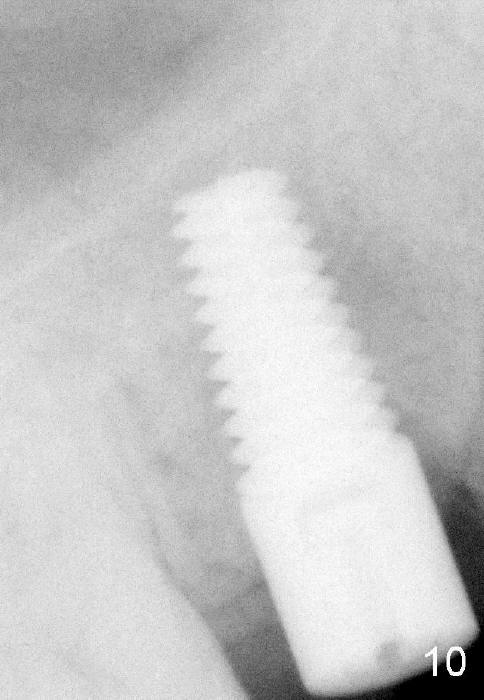

Four months after implant removal, the bony defect appears to increase (Fig.5). Reamers (Fig.6 R)and osteotome (Fig.7 O) are short of the sinus floor (arrowheads). A 5x14 mm tapered implant is placed with primary stability (Fig.8 I). The implant is placed ~ 2 mm deeper (Fig.9). No bone graft is used for sinus lift. There is no complication. The sinus floor appears to be repaired 4.5 months postop (Fig.10). Fig.11 (trimmed from panoramic X-ray) is taken 1 year 7 months post cementation. The bone remains stable 4 years 2 months post cementation (Fig.12); the mesial defect is most likely related to extraction trauma (*).